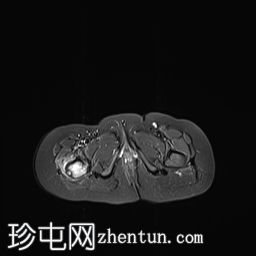

髋部

MRI

冠状位

T1

右上股骨大转子正下方外侧皮质区可见一小的皮质基部病变,边缘呈低信号,大小约为0.7 x 0.7厘米。

邻近的股骨近端骨干和股骨颈有水肿。

水肿有扩散至邻近肌肉的迹象。